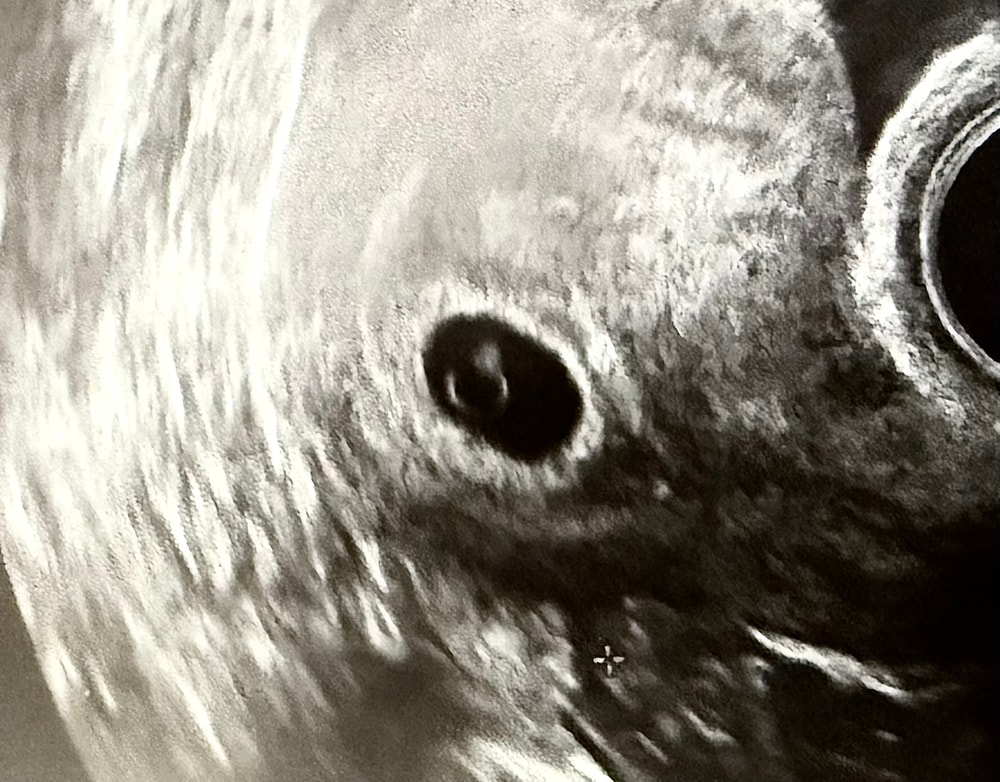

21 дпп (24.11) была на узи, ре очень быстро посмотрела все на месте, сказала все ок, и что не будем его долго тревожить, что вот жм, эмбрион и даже, как пульсацию увидела и сказала, что сейчас уже формируется сердечная трубка (фото этого кольца с бриллиантом 💍 приложу , эмбрион 6 дневный - 3 ВВ, после пгт). Договорились, что уже 11.12 приеду на финальное узи для точных замеров и дальнейших рекомендаций. Уменьшаем поддержку с 4 т дюфасиона переходим на 3, с 3 т прогиновы переходим на 2, добавляем магний , через 5-7 дн эстрожель отменяем 3 наж, остальное остается клексан, 2 ипрожина утром и вечером ,ну и все витамины какие и были.

Смотрит узи и О ЧУДО!, говорит вижу эмбрион, и что произошли отслойки что ли, (я была просто не вменозе и не совсем помню, что он точно сказал) я ему показываю своё узи, он говорит да точно такое же и я вижу и говорит : «Давай поборемся за этого ребенка!» 😢🙏🏼реееву…